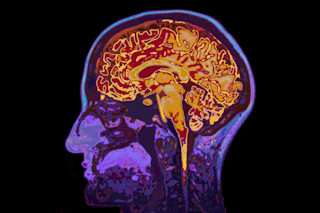

If you look at the brain of an , you’ll see clear and undeniable damage.

Clusters of dead nerve cells. Hard plaques cemented between cells and thick tangles of proteins twisted up inside the cells themselves.

These are the hallmarks of Alzheimer’s, and they drive the disease’s infamous symptoms, like memory loss, behavioral issues and problems thinking.

With brain imaging and other techniques, researchers have been digging into the roots of the proteins associated with Alzheimer’s disease for decades. We now have a good idea of how they form, but it’s the why that’s missing.

But with brain imaging and early detection, researchers are now able to study these proteins long-term, watching them accumulate as the disease progresses. Many think that if we can watch them build up, we can find a way to break them back down — ultimately . That’s easier said than done, of course, because both tau and beta-amyloid proteins wreak havoc in their own, separate ways.